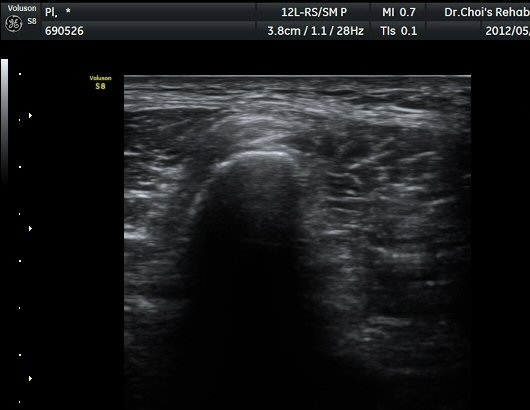

ŽÃËÀÚ¸¦ ´õ ¾Æ·¡·Î À̵¿ÇÏ´Ï Ãµºñ°ñ½Å°æÀÌ Àú¿¡ÄÚ µÕ±Ù µ¢¾î¸®·Î °üÂûµÇ´Ù°¡ ´Ù½Ã Á¤»óÀûÀÎ ¸ð½ÀÀ¸·Î °üÂûµÈ´Ù(±×¸² 7, 8).